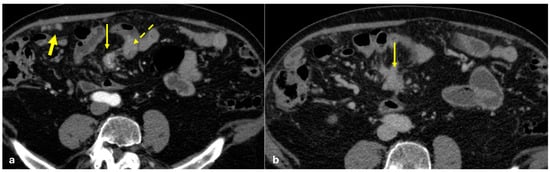

3.1.2. Peritoneal Mesothelioma

3.1.3. Peritoneal Localizations of GIST–Peritoneal Sarcomatosis